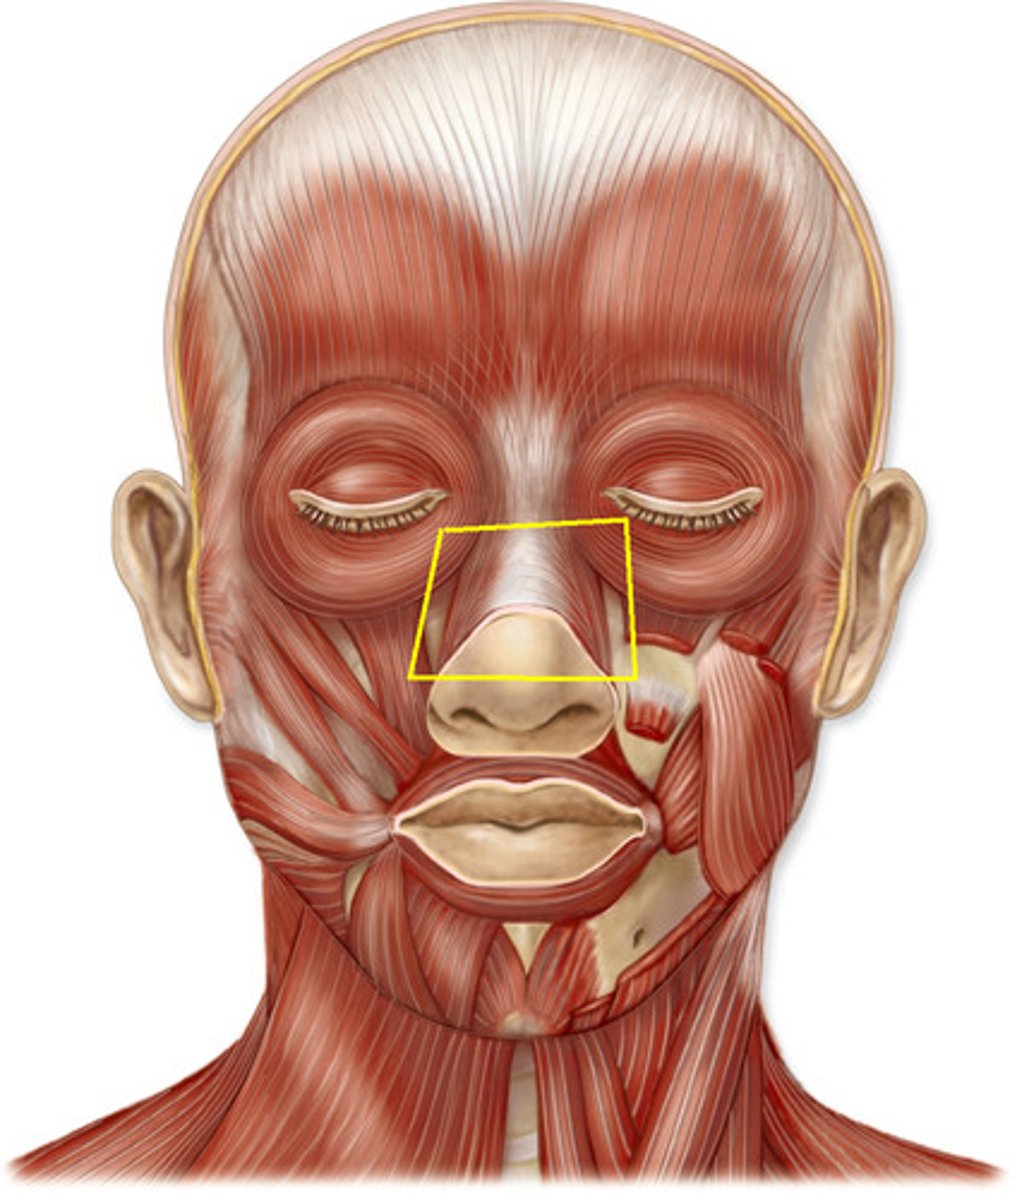

Procerus m.

Origin: Bridge of nose

Insertion: Skin between eyes

action: Depress eyebrow

Nasalis m.

Origin: maxilla

Insertion: Nasal Cartilage

Action: Compress nares

Levator labii superioris m.

Origin: maxilla

Insertion: superior lip

Action: elevate